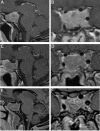

Acromegaly is a disease that occurs secondary to high levels of GH, most often from a hormone-secreting pituitary adenoma, with multisystem adverse effects. Diagnosis includes serum GH and IGF-1 levels, and obtaining an MRI pituitary protocol to assess for a functional pituitary adenoma. Attempted gross total resection of the GH-secreting adenoma is the gold standard in treatment for patients with acromegaly for a goal of biochemical remission. Medical and radiation therapies are available when patients do not achieve biochemical cure after surgical therapy.